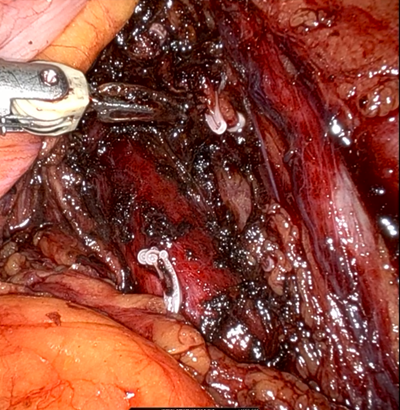

10、 肿瘤后外侧与周围组织粘连紧密,游离中小动脉发生出血。双机械臂交替辅助暴露并压迫出血点,马里兰钳电凝止血。助手及时负压吸引积血,发现是第二支肿瘤后外侧滋养血管,hem-o-lok夹闭血管后,创面电凝,出血控制。

11、 标本完整游离后,充分暴露创面并确切止血。无活动性出血后填以可吸收纱布,留置引流。